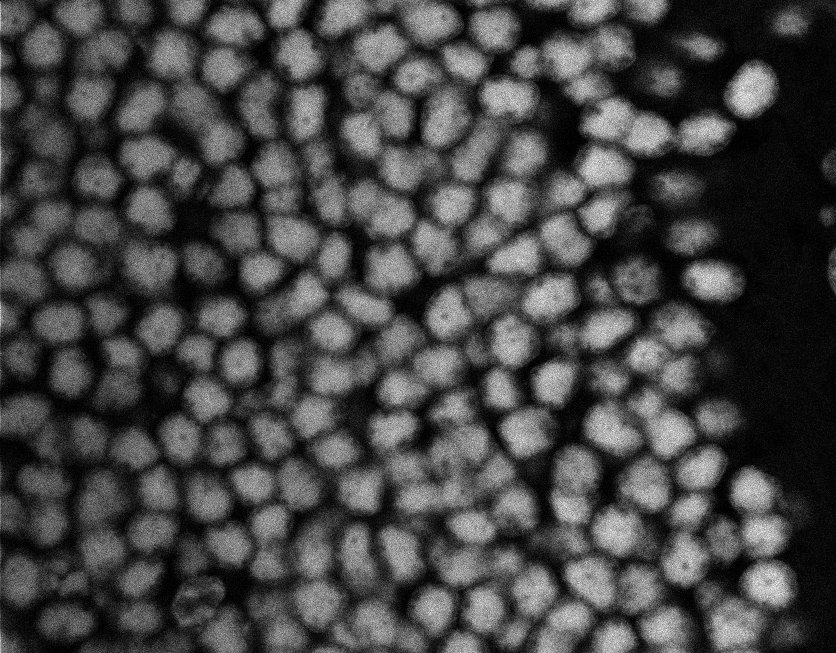

Nuclei

Nuclei - Bis

Nuclei - Bip